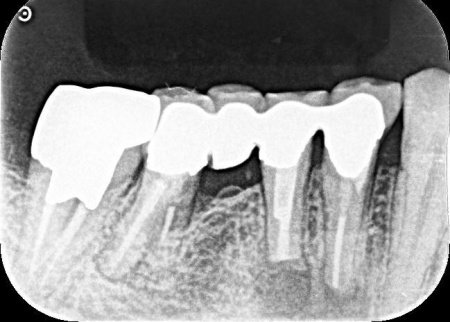

| 診断 | 拝見したところ、右下の奥歯周辺の歯ぐきが腫れていました。

歯やあごの骨の状態を詳しく調べるためレントゲン検査を行った結果、右下の奥歯2本(第2小臼歯、第1大臼歯)は、歯根が縦方向に割れている可能性が高いと考えられました。 しかし、レントゲン画像だけでは歯根の状態を正確に判断することはできません。 歯根が割れている場合、細菌感染が進行して歯ぐきの炎症が広がったり周囲の歯やあごの骨にまで影響を及ぼしたりする可能性があります。 以上のことから、歯を温存することは難しいため抜歯が必要と診断しました。 |

| 診断 | 拝見したところ、左下の一番奥の歯(第2大臼歯)の歯茎に腫れが認められました。 レントゲン撮影を行って詳しく調べたところ、歯根が縦方向に割れている「歯根破折」が疑われる状態です。 歯根破折は、過去に神経の治療を行った歯に起こりやすいトラブルで、今回のケースでは被せ物の下で破折が進行していたと考えられます。 このまま放置すると、痛みや腫れを繰り返すだけでなく、周囲の骨が溶けて隣接する歯にも悪影響を及ぼすおそれがあるため、抜歯の必要があると診断しました。 |

歯根破折が疑われました。